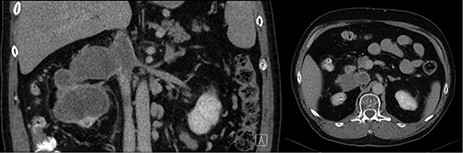

A 58-year-old fit gentleman presented in the mid of 2016 with a large RCC extending into IVC to the liver and multiple lung metastases. It was decided at that time not to do any surgical intervention and to treat solely with Sunitinib. Regular radiological follow-up did show a stable disease, and there was no significant side effects related to Sunitinib. In October 2018, follow-up CT showed complete resolution of lung metastases and extensive thrombus in the IVC extending from iliac bifurcation to the liver, as showed in Fig. 1 [1]. Surgery was done doing radical nephrectomy and complete IVC thrombectomy.

Pre-operative coronal and axial CT images showing right kidney tumor with a large tumor extension into the IVC.